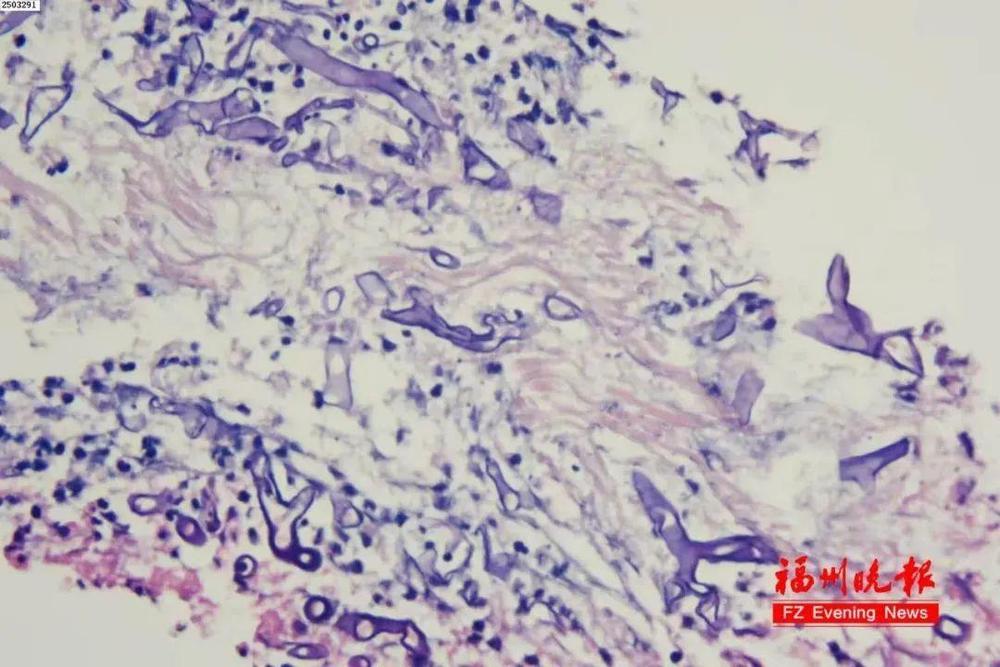

△患者病理切片

福建福州的强叔(化名)因反复咳嗽、肺部多发结节就医,曾被怀疑过恶性肿瘤或细菌感染性祸首肺炎,没想到近期终于查出罪魁—— 毛霉菌。

福州市第一总医院呼吸与危重症医学科主任徐礼裕表示,强叔所患的肺毛霉菌病致死率很高。而让强叔不堪一击的根源,正是他 长期失控的血糖。